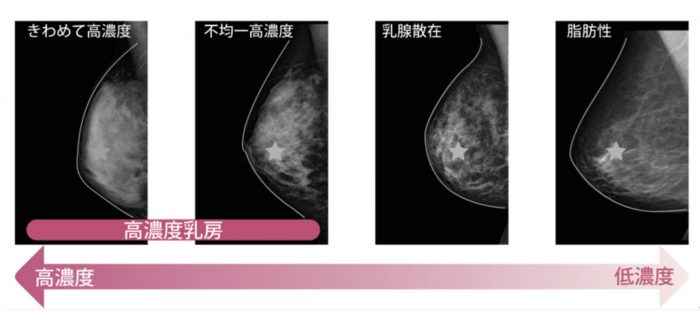

日本には「高濃度乳房」と言われるマンモグラフィでは病変がわかりにくい乳房を持つ女性が7〜8割であると言われている。高濃度乳房に対しては、マンモグラフィと乳房超音波検査の総合判定が有効であると明らかになっているため、資金助成の実施を求めた。高濃度乳房は乳がんの発症リスクが増加することは確実であるとわかっている。米国の高濃度乳房の女性の割合は4割程度という数字と比較すると、日本女性にはマンモグラフィだけの検診では不十分であることが分かる。

▲写真 乳腺濃度は,乳腺と脂肪の割合や分布によって,『極めて高濃度』,『不均一高濃度』,『乳腺散在』,『脂肪性』の4つに分類されている。前者2つ、図の左2つを高濃度乳房と呼ぶ。 出典 埼玉乳がん検診検討会